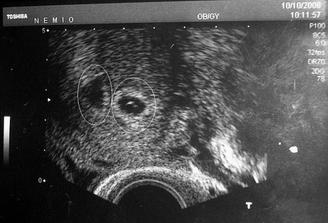

18.září jsme byli na našem 1.IVF... a 8.den od ET se mi "zjevily" nádherné // 🙂... přeju si,aby se všechno vyvíjelo dobře... 29.9 11.den po ET mi pro zhoršení OHSS provedli punkci Douglasova prostoru a odsáli 2 litry žlutého ascitu ☹ Nicméně se mi ulevilo 🙂 HCG ten den 259... 6.10 kontrola HCG - 2950 (18.den od ET)... 10.10 UTZ - čekáme DVOJČÁTKA 🙂 🙂 🙂... 17.10 krvácení a následná hospitalizace, UTZ - dvojčátkům bijí srdíčka, 20.10 HCG - 56000, 25.10 propuštění z nemocnice... 31.10 poslední kontrola v CARu, dvojčátka mají 2 a 2,1 cm... 11.11 UTZ - dvojčátka mají 3 cm... 24.11 UTZ - dvojčátka mají 9 cm (ale moc se mi to měření nezdá, ve čtvrtek na screeningu se ukáže pravda, čeká nás 3D 🙂) 27.11 screening I.trimestru - miminka jsou zdravá, od hlavičky po prdelku mají 7 cm... 19.12 3D - miminko "A" je chlapeček, "béčko" chce zůstat zatím v utajení 🙂 tak snad příště 🙂... 8.1 3D - miminko "B" je holčička 🙂 19.1 echokardiografie - obě srdíčka jsou zdravá 🙂 20.1 screening II.trimestru - vše OK, miminka mají 360 a 364 gramů 🙂 26.1 UTZ - chlapečkovi se ztratil pindík a najednou čekáme 2 holčičky 🙂) Doufám, že už je to definitivní 🙂) 19.2 UTZ 3D4 - holčičky potvrzeny!!! 🙂 mají každá téměř 800 gramů! 🙂 20.3 UTZ - holčičky mají 1700 a 1800 gramů! 8.4 UTZ - holky mají neuvěřitelné váhy 2415 a 2600 gramů! 11.5 nástup do nemocnice... 11.května ve 20,03 se nám akutním císařským řezem narodila Eliška (2970/48) a o minutu později Nelinka (3200/50).Jsme nejšťastnější rodiče na světě! 🙂